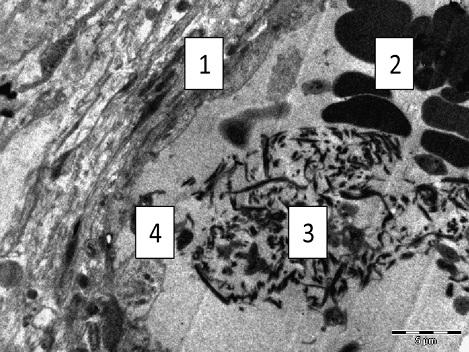

Электронно-микроскопическое исследование плаценты при ПОНРП выявило следующие морфофункциональные особенности: цитоплазма синцитиотрофобласта визуализировалась ячеистого вида из-за резкого расширения просветов канальцев эндоплазматической сети; в местах разрушения канальцев были видны очаги локальной деструкции; митохондрии — набухшие, отмечалась деструкция крист, просветление, а порой опустошение митохондриального матрикса; ядра визуализировались неправильной формы, деформированые; хроматин гомогенного вида; микроворсинки распределялись равномерно, но строма ворсин была разрыхлена, отечная, в строме просматривалось обилие мононуклеаров. Присутствовало нарушение межклеточных контактов между децидуальными клетками. Большинство просмотренных сосудов резко полнокровны, в просветах видны сладжированные эритроциты. В просвете некоторых сосудов наряду с эритроцитами выявляются скопления тромбоцитов, нити фибрина, адгезия тромбоцитов к эндотелию; также визуализировалась межклеточная локализация фибрина. В некоторых ворсинах определяются массивные кровоизлияния с пропитыванием стромы (Рисунки 1, 2, 3, 4). Таким образом, при изучении морфологической архитектуры ткани плацент при ПОНРП четко прослеживается морфофункциональная характеристика плацентарной недостаточности и наличие ультраструктурных характеристик ее декомпенсации.

Рисунок 4. Срез плацентарного сосуда при ПОНРП — набухание эндотелия (1), тромбоциты (2), нити фибрина (3), агрегация тромбоцитов к эндотелию (4). (Родильница С., 27 г.). Ув. х2800

Figure 4. Section of placental vessel in PONRP — swelling of the endothelium (1), platelets (2), fibrin threads (3), platelet aggregation to the endothelium (4). (Mother S., 27 years old). Magnification x2800